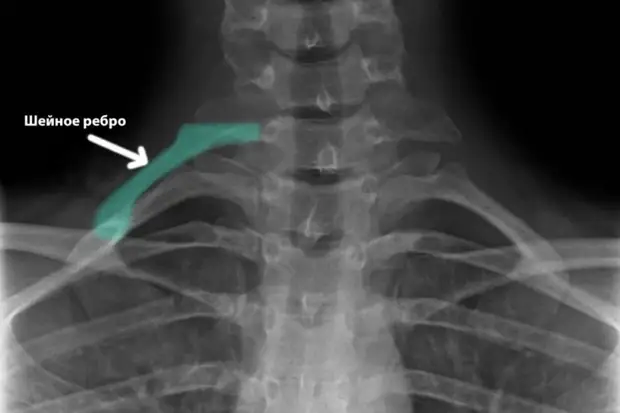

Медицина и диагностика: Аномалии ребер на рентгене